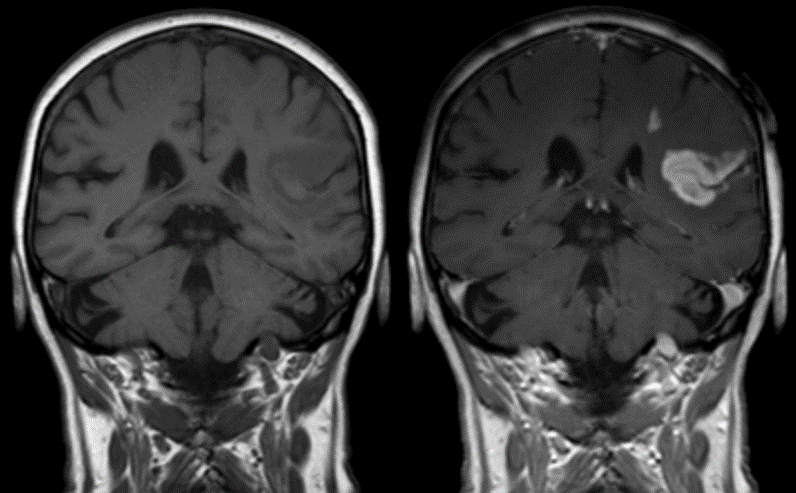

Jeffrey Struss Associate Scientist, Nanomaterials Magnetic Resonance Imaging (MRI) is one of the most commonly used non-invasive imaging techniques in medicine. Allowing the clinician to visualize the structure of the tissues inside the body in high resolution without the need for vivisection. With the dramatic enhancements to in vivo imaging and the growth of cellular-based therapeutics, the need to track cells as they travel, over time, through the body has continued to grow. Whether immune cells, stem cells, cancer cells or native cells, the ability to see how cells travel and congregate throughout the body can provide great insight into various issues such as cancer, auto-immune disorders, wound healing and aging. One of the ways to improve imaging in MRI applications is via the introduction of a contrast agent. Contrast agents interact with the magnetic fields of the MRI to enhance the appearance of internal biological structures. The image below shows a stroke patient before the administration of a contrast agent (left) and post administration of a contrast agent (right). The use of the contrast agent in the right image makes it very clear where the stroke occurred and the magnitude of tissue affected by the stroke.